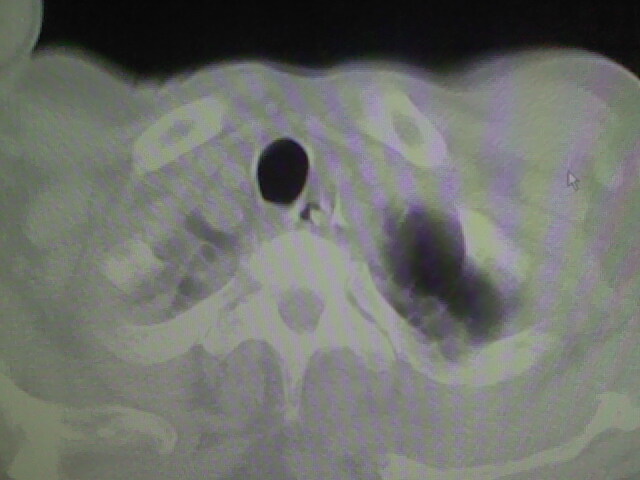

男,70岁,脑出血,长期卧床,左侧背部可触及肿块

肺部感染,背部筋膜增厚,考虑坠积性水肿或炎症

食道里是什么

你放上去的